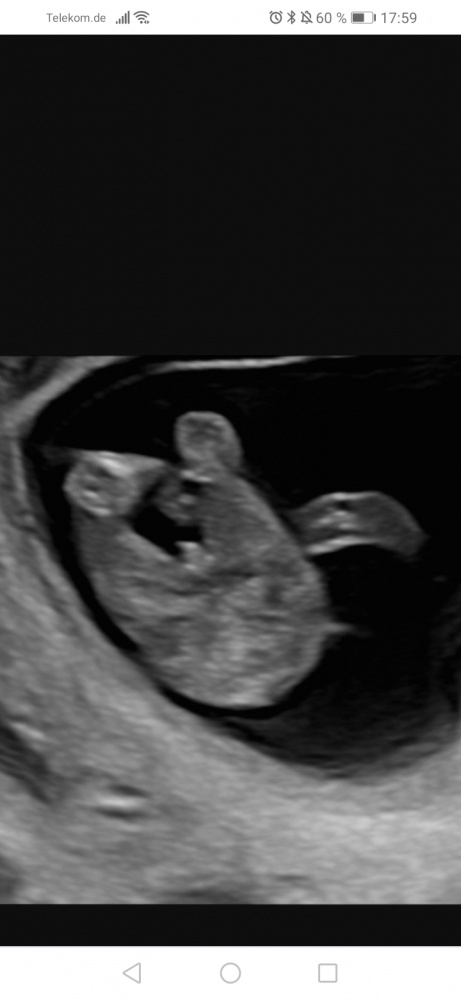

Hallo. Ich war diese Woche bei meiner Frauenärztin (17+1) und sie war sich beim Geschlecht sofort sicher

Was sagt ihr? Ist es wirkich ein Junge? <br>

Was sagt ihr? Ist es wirkich ein Junge?